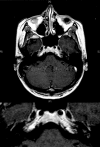

Cogan's syndrome is defined as a chronic inflammatory disease of unknown origin, an autoimmune disease, characterized by bilateral sensorineural hearing loss, vestibular symptoms, inflammatory ocular manifestations with variable risk of developing into a systemic disease. The onset of disease is variable but is often characterized by isolated ocular symptoms or acute ear and/or vestibular manifestations, variably associated. The diagnosis of Cogan's syndrome can be a challenge as is evident in the case described here since it is based only on the association between bilateral ocular and vestibuloauditory symptoms with no specific diagnostic tests available.